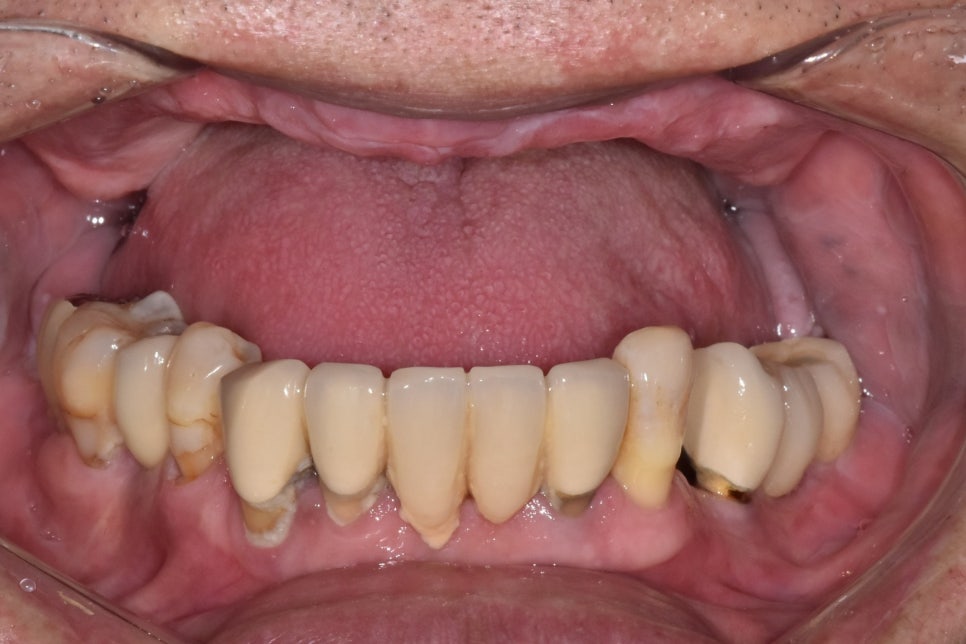

이 환자분은 위에 치아가 하나도 없으셔서

완전 틀니를 쭉 사용해 오셨대요.

오랜 시간 치아 없이 지내면

뼈가 점점 흡수되어 얇아지는데요.

이 환자분도 사진을 찍어보니

뼈가 많이 얇아져 있었습니다.